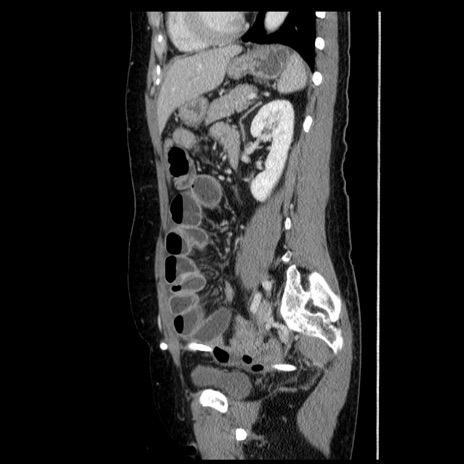

症例6(矢状断像)

【症例】50歳代女性

【主訴】下腹部痛

【既往歴】卵巣癌術後(8年前に当院で卵巣摘出)

【身体所見】 意識清明、腹部:平坦、腸蠕動音→、やや硬、下腹部自発痛・圧痛あり、反跳痛あり、筋性防御なし。

【データ】WBC 16000、CRP 0.01